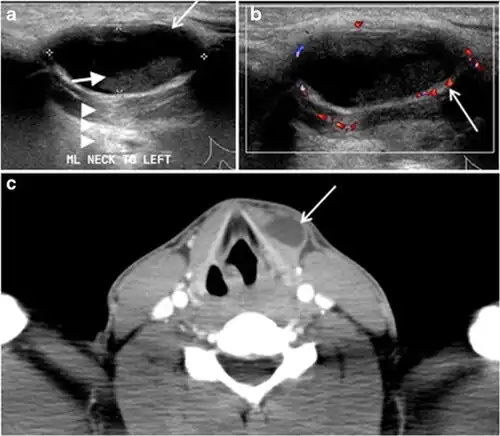

Fig. 7. A 51-year-old female patient post total thyroidectomy for PTC with elevated thyroglobulin measurement. an Axial non-enhanced CT scan of the neck at the level of the thyroid bed demonstrates a well-defined, rounded, homogenously dense soft tissue situated between the trachea and left internal jugular vein (white arrow). b Transverse ultrasound image of the neck demonstrates a well-defined, homogeneous, hypoechoic soft tissue nodule measuring 6 mm (white arrow) with no detected micro-calcifications. Biopsy showed a predominantly residual normal thyroid tissue with micro-foci of PTC.[1] -

Fig. 9. A 58-year-old male patient with persistence PTC at thyroid bed with hypervascular nodal metastasis. a–c Transverse greyscale and colour Doppler neck ultrasound demonstrate hypoehoic soft tissue in the left thyroid bed (white arrow in a). There are a heterogeneous enlarged lymph nodes at level 2 and 3 with markedly increased vascularity (white arrow in b and c). d–f Enhanced axial CT images of the neck demonstrate a 2.7 × 1.4 cm hypodense soft tissue lesion anterior to the left carotid sheath (white arrow). There are left-sided enhancing abnormal and enlarged lymph nodes at cervical level 2 and 3 (black arrows).[1]